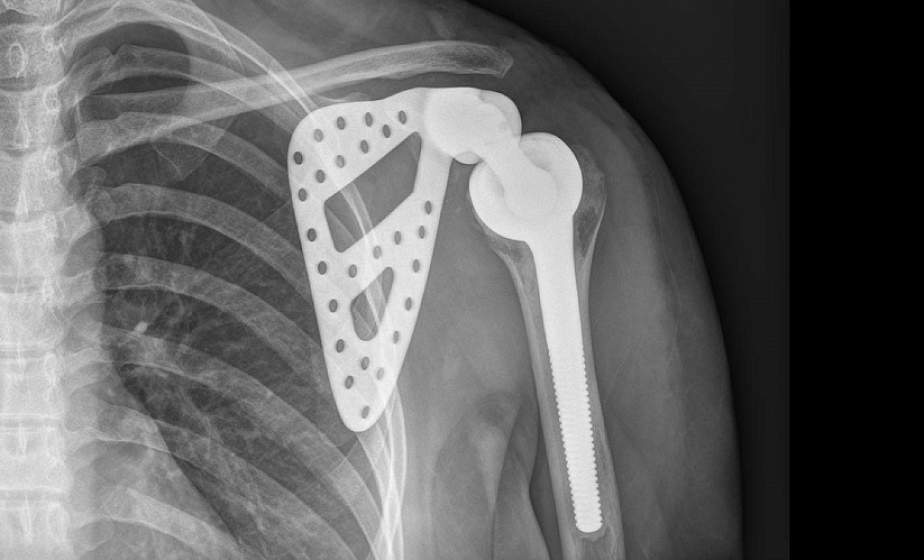

По словам директора института, в настоящее время ученые работают над созданием имплантатов из титана для различных направлений медицины: травматологии, кардиохирургии, стоматологии, хирургии позвоночника, ортопедии. "В нашем институте выполнен ряд инновационных проектов, в результате которых разработаны и освоены технологии точного формообразования полуфабрикатов изделий для эндопротезирования крупных суставов человека. Сегодня обеспечиваются потребности Министерства здравоохранения в эндопротезах тазобедренного сустава бесцементной фиксации. Разработаны эндопротезы коленного сустава из титана. Ведется подготовка к производству, и в ближайшее время эти протезы будут серийно выпускаться", - рассказал Виталий Залесский. Имплантаты из титана отличаются долговечностью (срок службы до 20 лет) и устойчивостью к биоразрушению - его без опаски можно вживлять в организм человека.

Ученые Физико-технического института НАН разработали также имплантаты с биосовместимыми защитно-декоративными покрытиями. Они более износостойкие по сравнению с обычными и лучше вживляются в костную ткань.